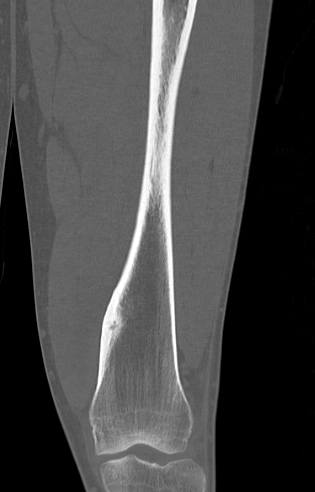

CT

Best investigation

- lucent nidus surrounded by dense bone

Osteoid osteoma tibia